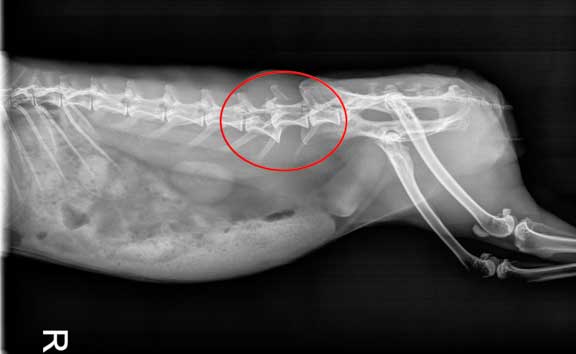

Anesthetic monitoring is important is such a small animal, and especially in rabbits that have such a small lung capacity compared to other animals of comparable size.

The heart and lungs (within the red circle) are tiny compared to the size of the abdomen. This ratio between lungs and abdomen is much smaller than in other animals, and needs to be closely watched during anesthesia.